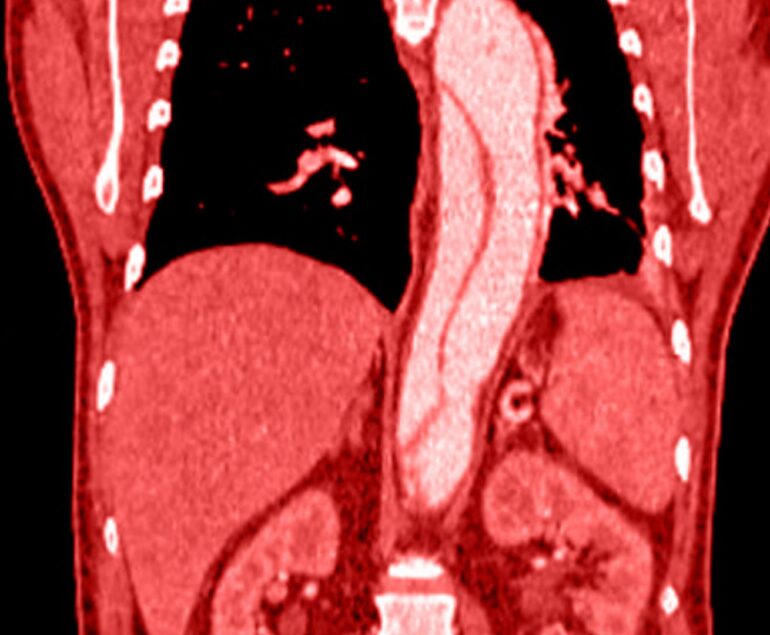

Patologie del distretto arterioso

Diagnostica, chirurgia e trattamenti del distretto arterioso